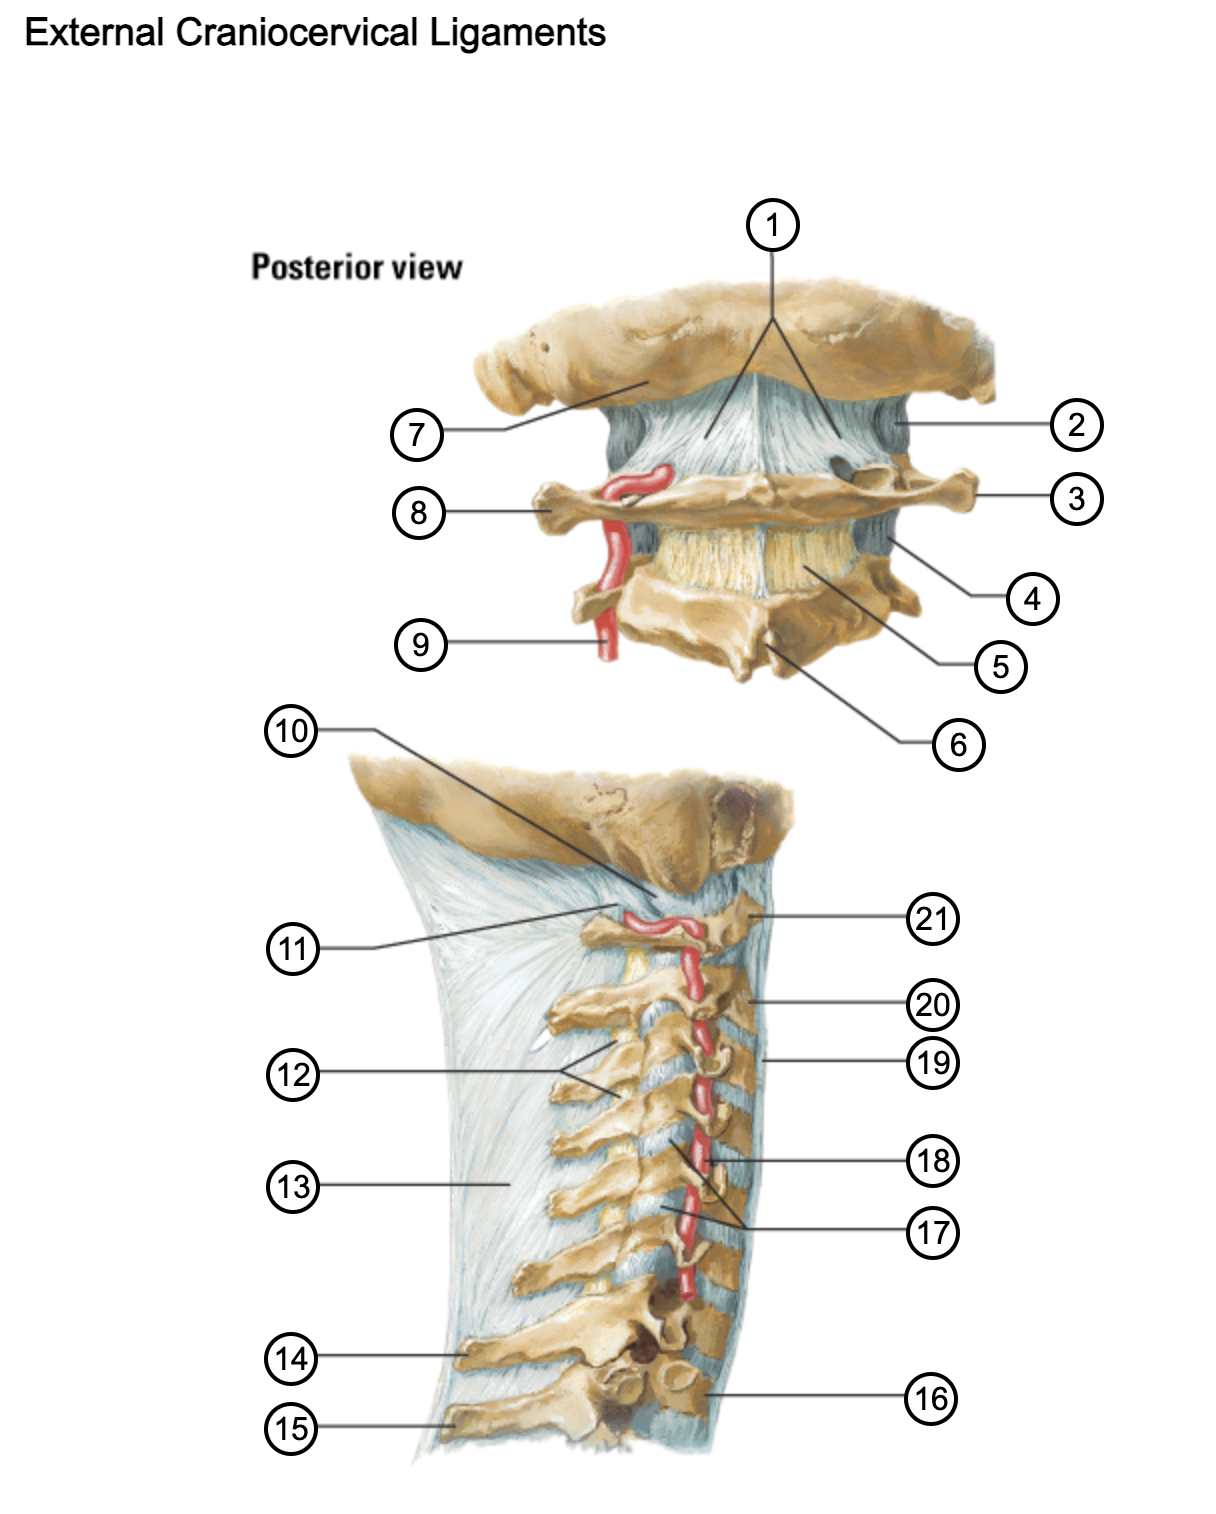

1

posterior antlantooccipital membrane

2

capsule of atlantooccipital joint

3

transverse process of atlas (C1)

4

capsule of lateral atlantoaxial joint

5

ligamenta flava

6

spinous process

7

occipital bone

8

transverse process of atlas (C1)

9

vertebral artery

10

capsule of atlantooccipital membrane

11

posterior atlantooccipital membrane

12

ligamenta flava

13

nuchal ligament

14

spinous process of C7 vertebra

15

spinous process of T1 vertebra

16

T1 vertebra

17

zygapophysical joints (C4-5 and C5-6)

18

vertebral artery

19

anterior longitudinal ligament

20

body of axis

21

Atlas (C1)